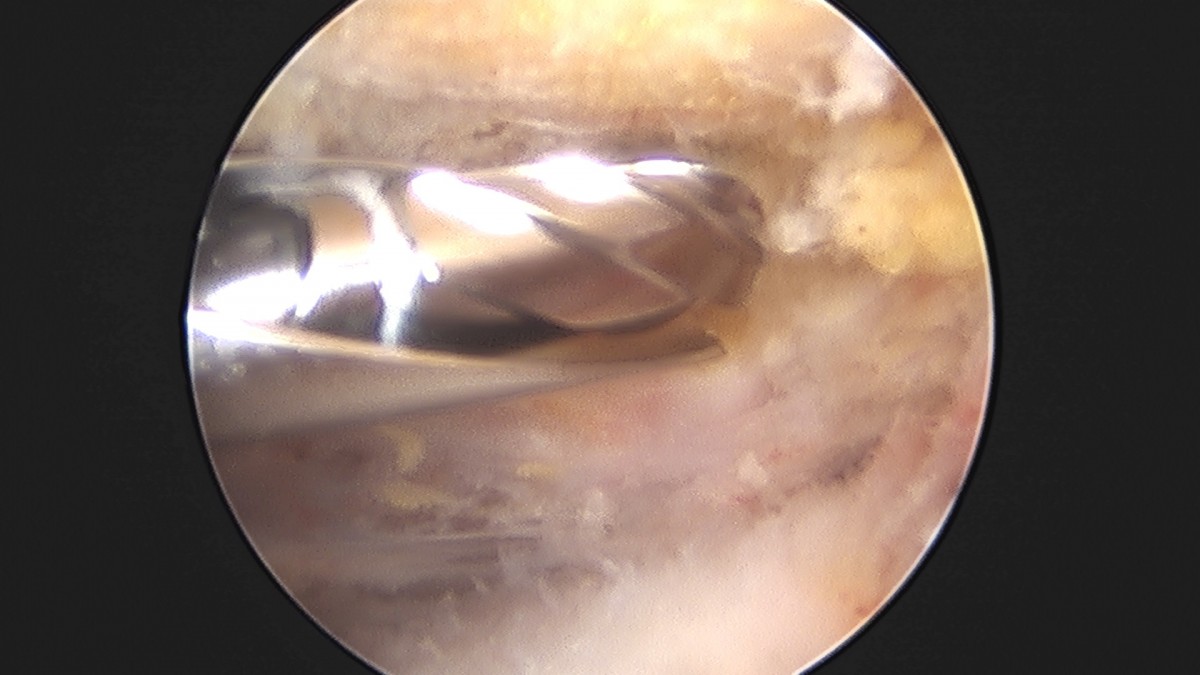

이재상원장님 어깨 견봉하 감압술 및 석회 제거술 이형O 환자

작성자 최고관리자 댓글 0건 조회 746회 작성일 25-09-16 15:40